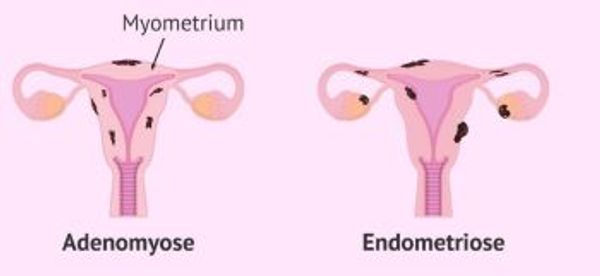

Adenomyose

Eine besondere Form der Endometriose ist die Adenomyose. Bei der Adenomyose befindet sich das Endometriosegewebe in der Gebärmutterwand, inmitten des dort vorhandenen Muskelgewebes. Adenomyose tritt auf, wenn die innere Schleimhaut der Gebärmutter in die darunter liegende Muskelschicht einwächst. Diese Stellen beginnen während der Menstruation zu bluten. Dadurch entstehen Hohlräume in der Muskelschicht, die mit altem Blut gefüllt sind. Dadurch vergrößert sich die Gebärmutter. Diese Hohlräume können große Schwellungen in der Gebärmutterwand verursachen, die einem Myom sehr ähnlich sehen. Eine solche Schwellung wird als Adenomyom bezeichnet und besteht im Gegensatz zu einem Myom, das aus Muskelgewebe besteht, aus Schleimhautgewebe. Adenomyome sind in der Regel sehr viel schmerzhafter als Myome, die in der Regel nur ein beklemmendes Gefühl verursachen. Sie verursachen nicht nur Schmerzen, sondern auch starke Menstruationsbeschwerden.